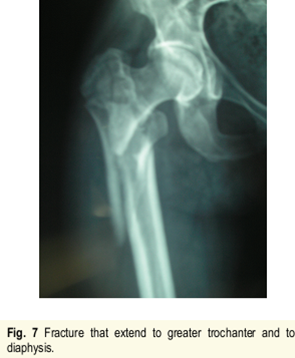

进针点和力线很难把握,即使应用很巧妙的复位技术获得了术后很好的力线,避免了髋内翻,但如此大块的骨块劈裂游离不处理,会存在退钉和骨不连或者髓内钉断裂的风险。